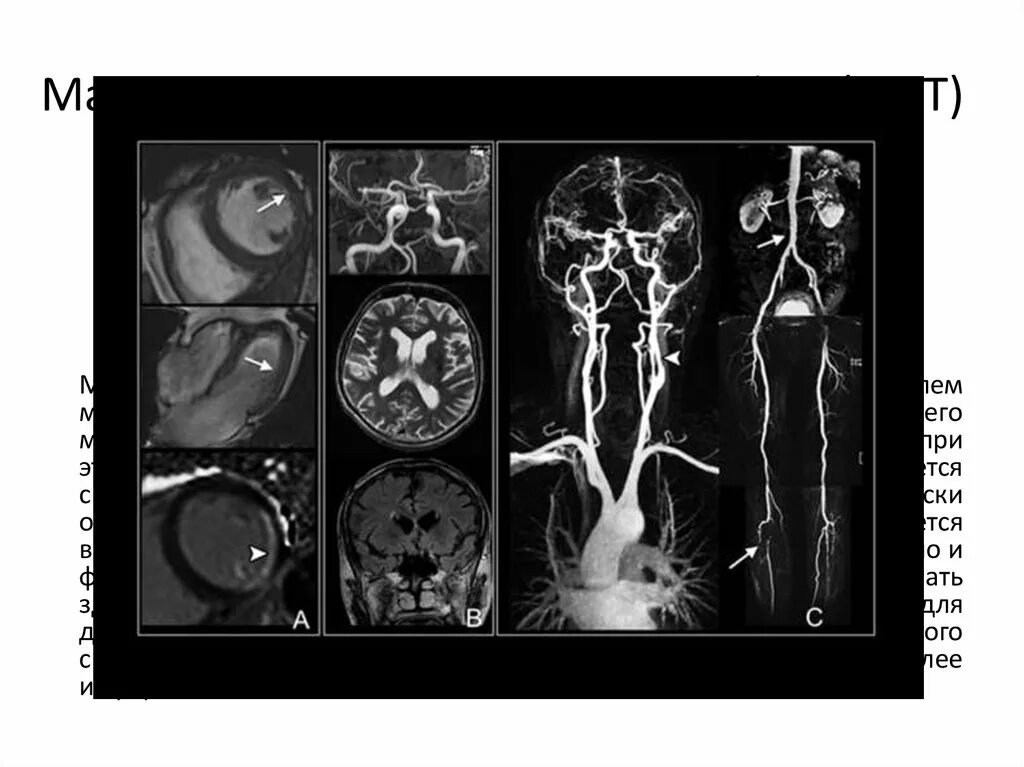

Можно заменить кт на мрт